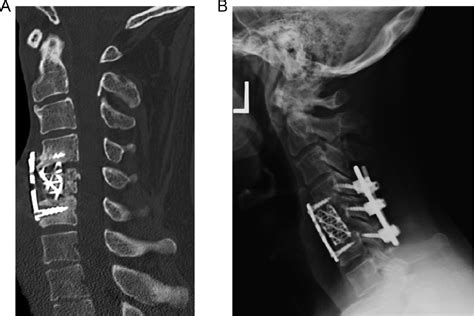

The Acdf Medical Abbreviation stands for Anterior Cervical Discectomy and Fusion. This is a surgical procedure performed to relieve pressure on the spinal cord or nerve roots in the neck. The procedure involves removing a herniated or degenerative disc in the cervical spine and then fusing the adjacent vertebrae to stabilize the spine.

The Surgical Procedure

The Acdf Medical Abbreviation procedure is performed under general anesthesia and typically involves the following steps:

1. Incision: The surgeon makes a small incision in the front of the neck.

2. Discectomy: The surgeon removes the damaged disc, relieving pressure on the spinal cord or nerve roots.

3. Bone Grafting: A bone graft is placed in the space left by the removed disc to promote fusion between the adjacent vertebrae.

4. Plating: A metal plate may be used to stabilize the vertebrae during the fusion process.

5. Closure: The incision is closed with sutures or staples.